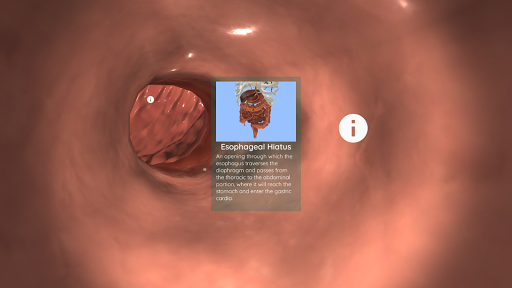

Anatomyou VR est une application mobile éducative qui présente l'anatomie humaine à l'utilisateur d'une manière immersive.

En utilisant la réalité virtuelle, vous serez capable de naviguer le long des structures anatomiques, devenant une partie de l'anatomie humaine: circulatoire, respiratoire, digestive, urinaire, lacrymale et système reproducteur féminin.

Ceci est une version récemment rénovée d'Anatomyou VR. Les fonctionnalités incluent: - Anatomie humaine plus réaliste, améliorant les modèles et les textures. - Meilleure interaction de l'utilisateur en mode VR et en mode plein écran. - Des menus et des images entièrement rénovés permettent une navigation intuitive. - Contenu clinique supplémentaire validé par nos experts. - Les utilisateurs précédents doivent accepter certaines autorisations (GoogleVR SDK). Nous avons mis beaucoup d'efforts dans cette mise à jour, j'espère que vous l'apprécierez!